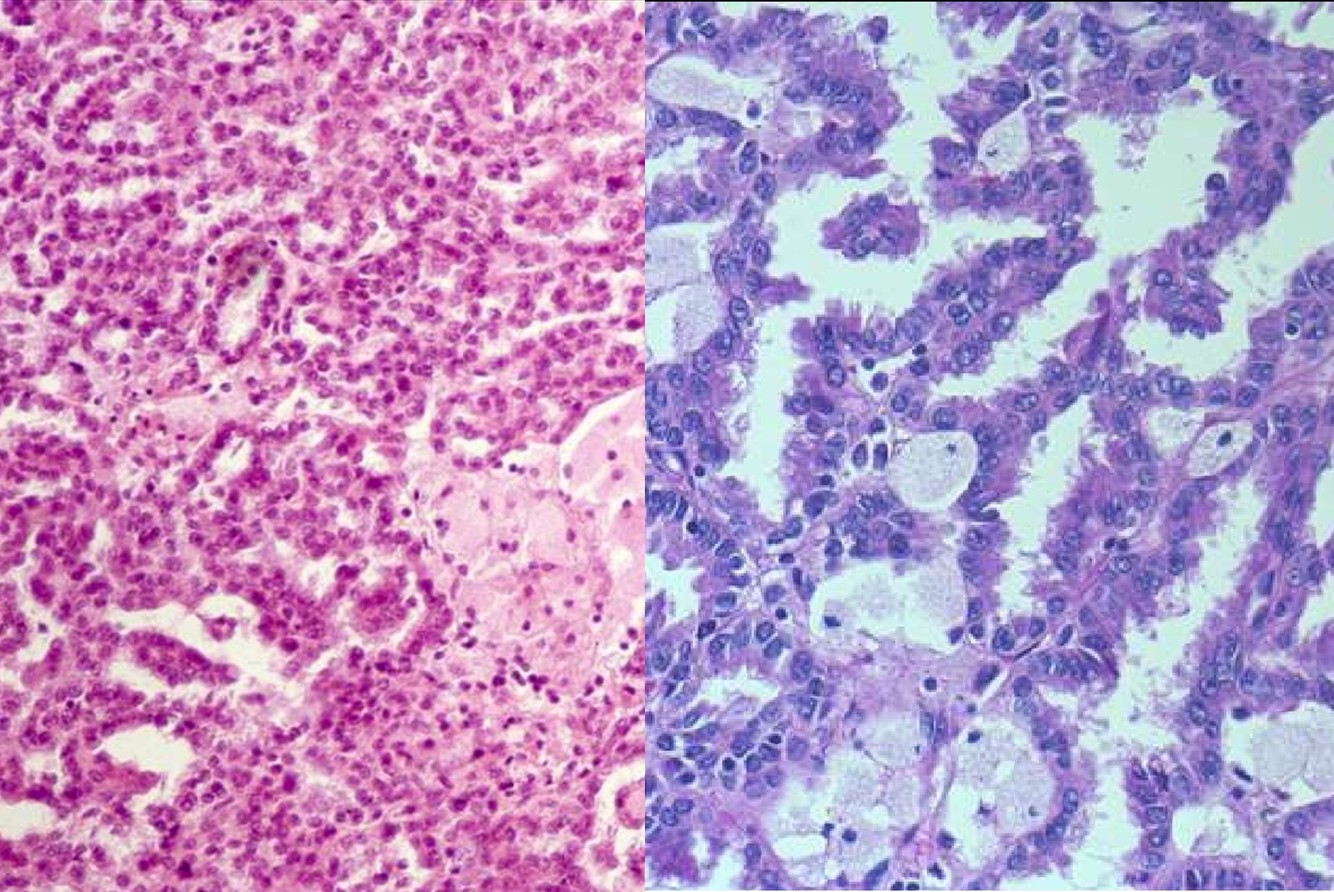

NEPHROGENIC ADENOMA

- Often associated with history of GU instrumentation, trauma or calculi

- GU tract, urinary bladder most common site

- Papillary tubulo-cystic growth pattern; hobnail nuclear contours

- IHC: PAX 8+, AMACR+

CLEAR CELL CARCINOMA OF GU TRACT

- Most commonly seen in female urethra

- Can be confused with nephrogenic adenoma

- PSA and PAP+